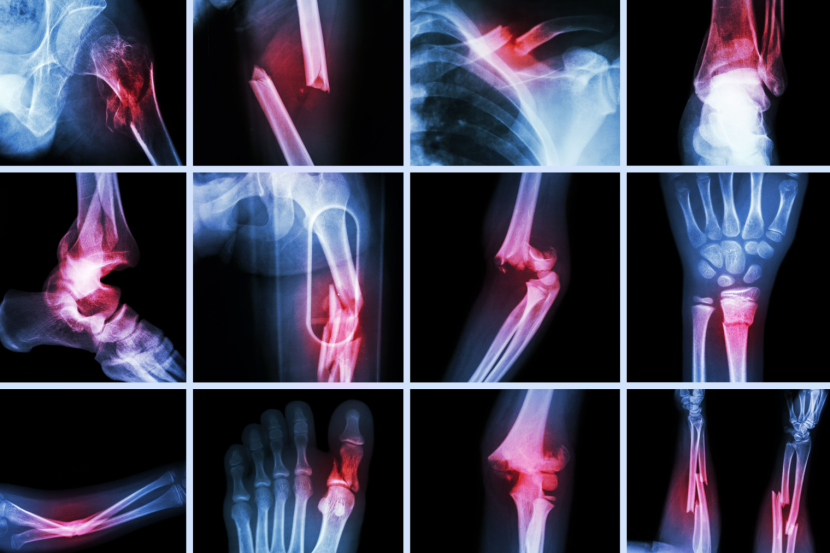

Lomovi kostiju mogu da se dese i dešavaju se svima. Stariji ljudi su više predisponirani za lomove, prvenstveno zbog smanjene gustine kostiju. Osteoporoza planetarno muči veliki broj osoba, a strah koji ovi pacijenti imaju od padova lomova je potpuno opravdan.